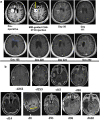

Immunotherapy failures can result from the highly suppressive tumour microenvironment that characterizes aggressive forms of cancer such as recurrent glioblastoma (rGBM)1,2. Here we report the results of a first-in-human phase I trial in 41 patients with rGBM who were injected with CAN-3110-an oncolytic herpes virus (oHSV)3. In contrast to other clinical oHSVs, CAN-3110 retains the viral neurovirulence ICP34.5 gene transcribed by a nestin promoter; nestin is overexpressed in GBM and other invasive tumours, but not in the adult brain or healthy differentiated tissue4. These modifications confer CAN-3110 with preferential tumour replication. No dose-limiting toxicities were encountered. Positive HSV1 serology was significantly associated with both improved survival and clearance of CAN-3110 from injected tumours. Survival after treatment, particularly in individuals seropositive for HSV1, was significantly associated with (1) changes in tumour/PBMC T cell counts and clonal diversity, (2) peripheral expansion/contraction of specific T cell clonotypes; and (3) tumour transcriptomic signatures of immune activation. These results provide human validation that intralesional oHSV treatment enhances anticancer immune responses even in immunosuppressive tumour microenvironments, particularly in individuals with cognate serology to the injected virus. This provides a biological rationale for use of this oncolytic modality in cancers that are otherwise unresponsive to immunotherapy (ClinicalTrials.gov: NCT03152318 ).

Figures